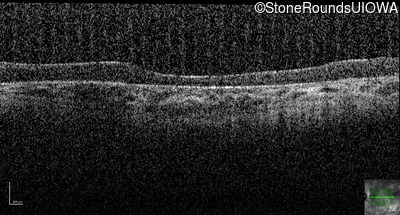

Optical Coherence Tomography - Right - 10/100 -2

Exemplar / OCT Stack